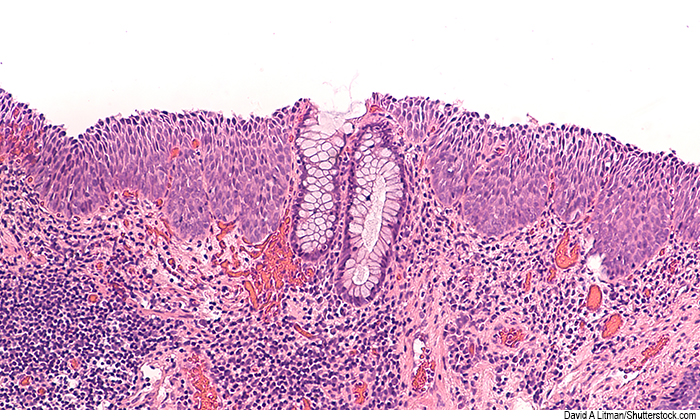

Like cervical cancer, anal cancer is caused by human papillomavirus (HPV), leading to precancerous high-grade squamous intraepithelial lesions that can progress to cancer.

“Treatment of high-grade cervical lesions is known to prevent cervical cancer in women,” notes Dr. Hagensee. “Anal cancer has Increased 25-fold in persons living with HIV, and the ANCHOR study is based on the same approach.”The ANCHOR (Anal Cancer-HSIL Outcomes Research) trial enrolled more than 4,000 people living with HIV who had high-grade anal lesions on biopsy at 25 sites in the US.